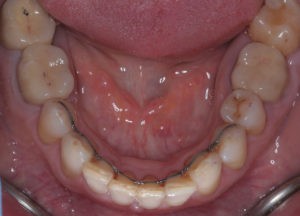

Искривление окклюзионной кривой (плоскости смыкания зубов), возникшее в результате парадонтита, успешно удалось устранить, используя накусочные брекеты на верхних резцах и микроимплант, установленный во фронтальном участке нижней челюсти: